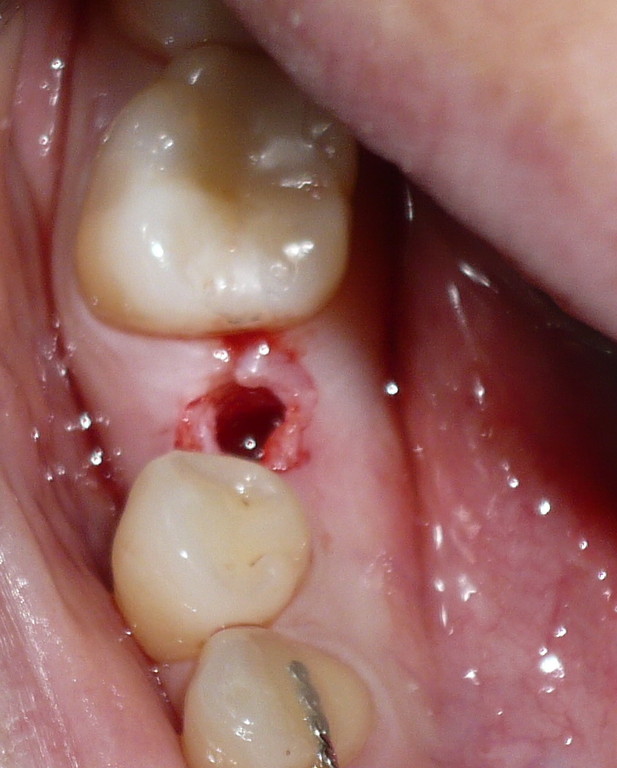

IMPLANTE INDIVIDUAL EN CARGA INMEDIATA-